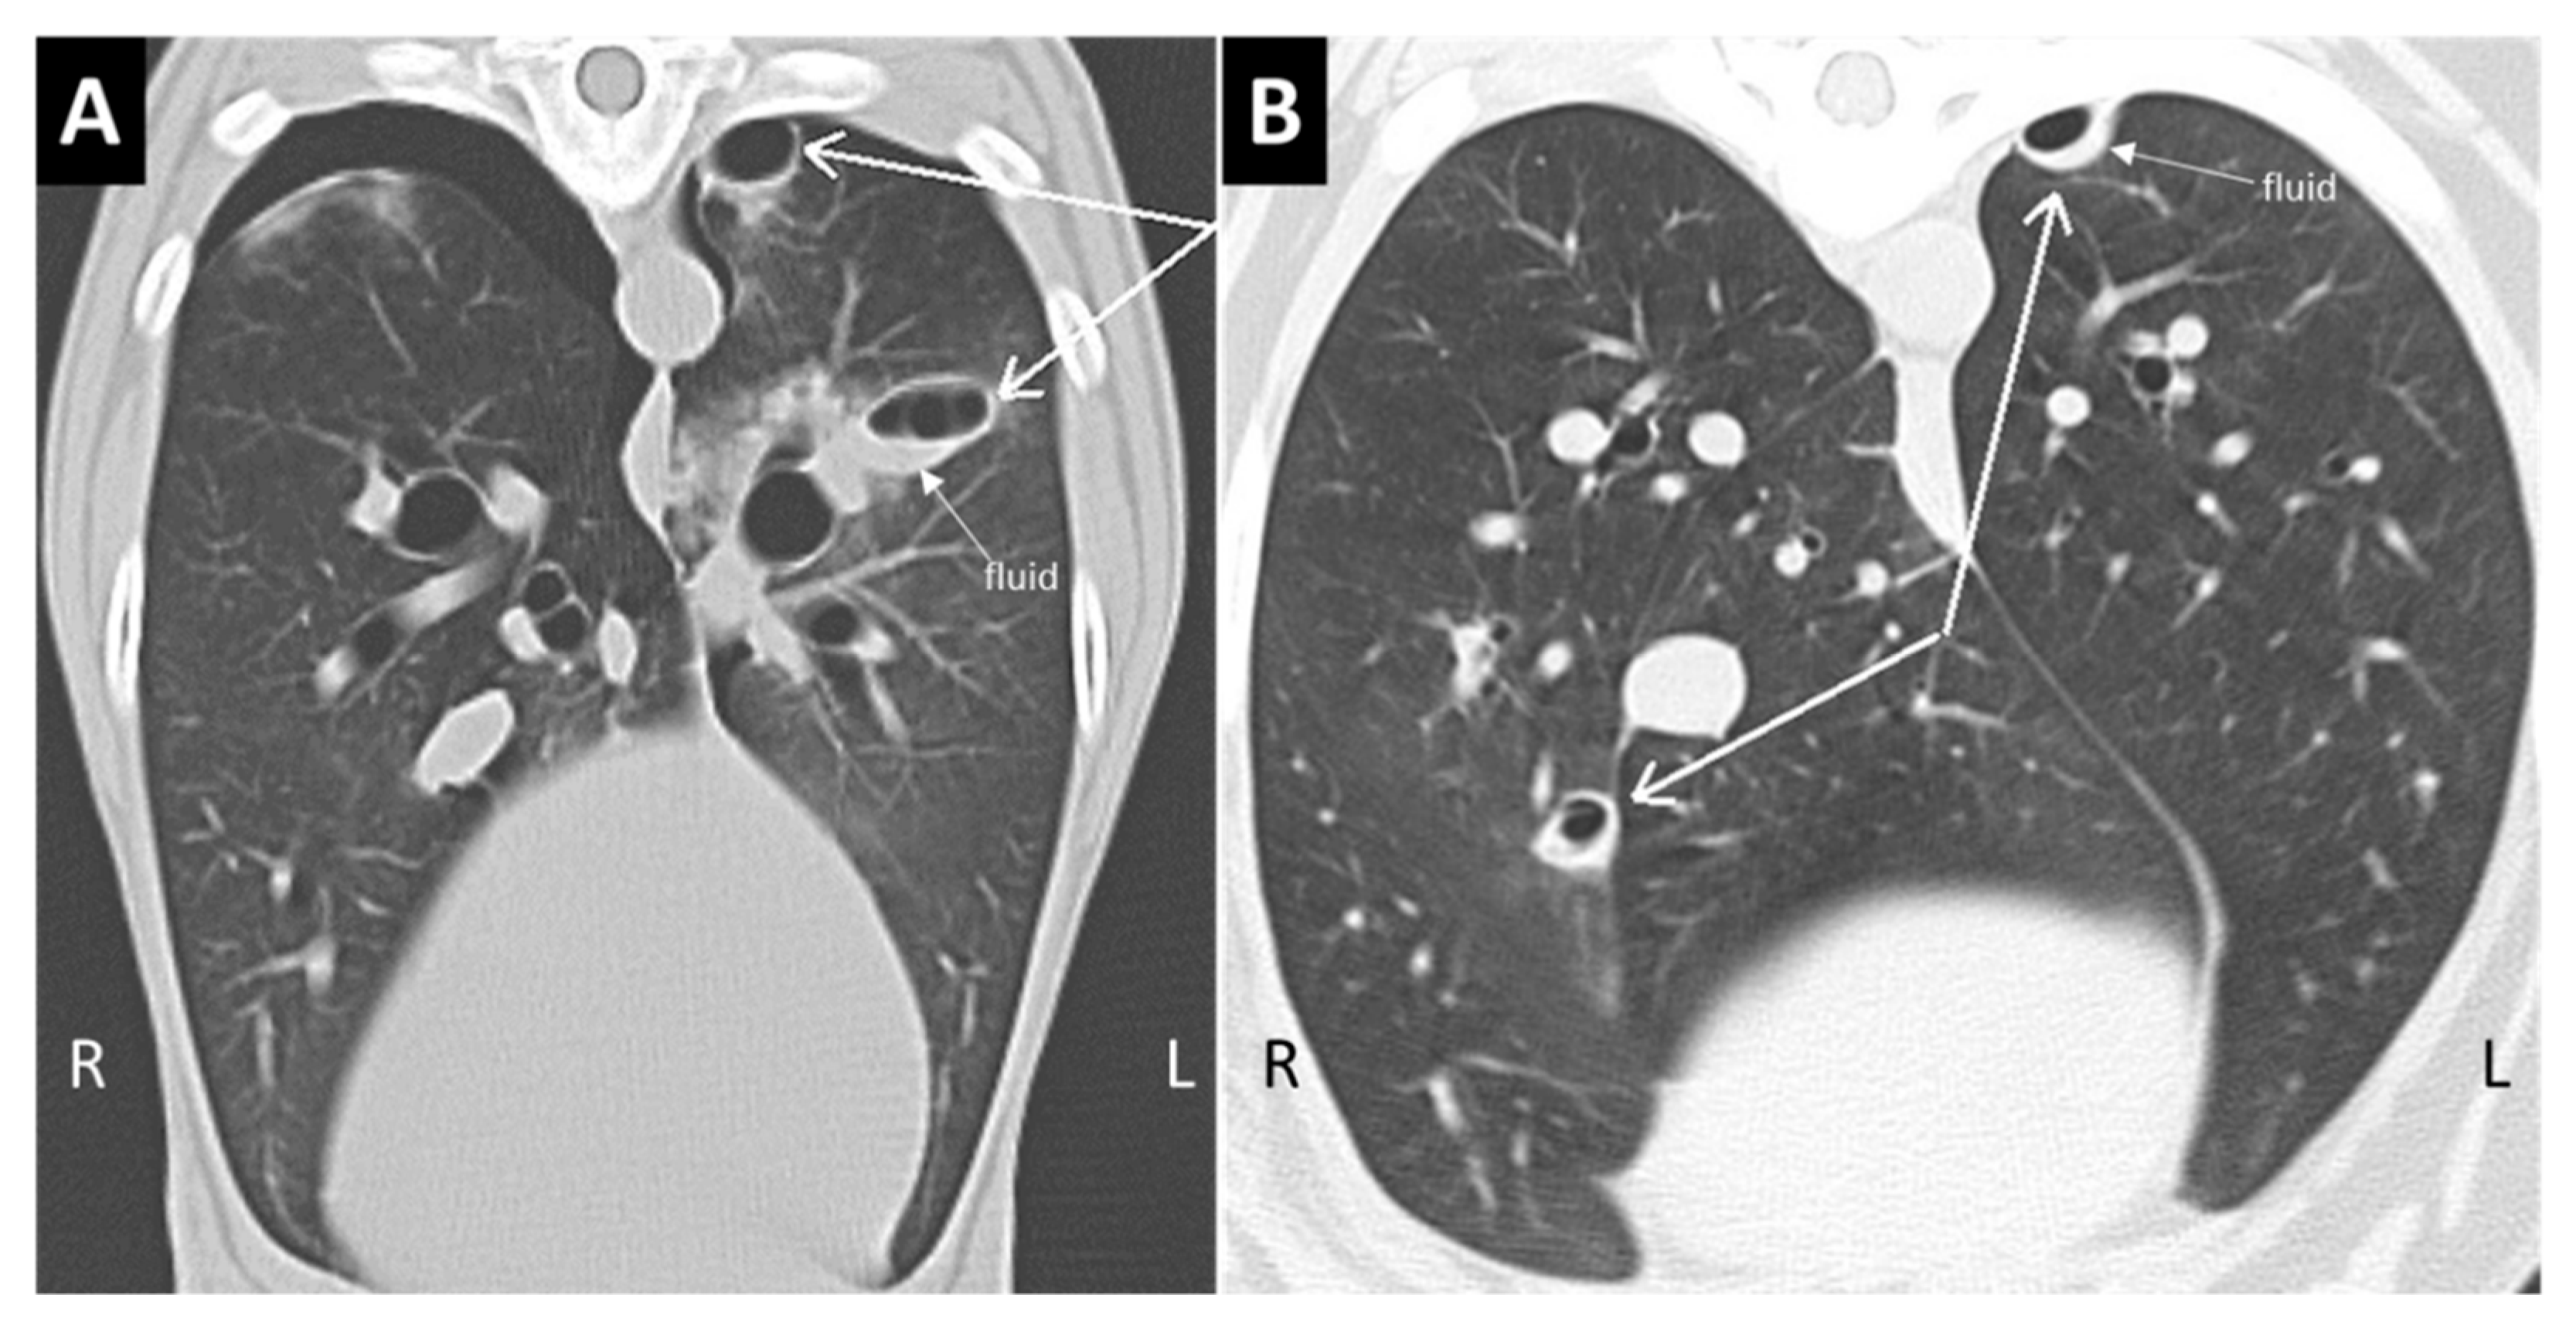

Figure 3.

Type 1 and Type 2 lung lacerations. (A) The transverse section of the thorax in a traumatized dog. In the left lung, there are two ovoid pseudocystic lesions, one located deep in the lung parenchyma and another in the subpleural area of paraspinal region, not associated with spinal fracture. Note the air–fluid level in the deep lesion in (A) and in the superficial lesion in (B) (pneumohematocele). Pneumothorax is present on the right side. (B) The transverse section of another traumatized dog with small Type 1 and Type 2 lung lacerations, both with mixed air–blood content. The dog had no vertebral fractures.